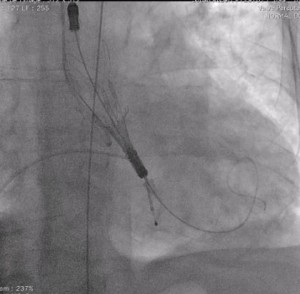

Acurate Neoの留置方法には特徴があります。Evolut Rの場合心室側から弁が展開しますが、Acurate neo TFの場合、大動脈側から展開します。実際の操作にも特徴があり、展開は二段階式になっています。一段階目は大動脈側が展開し、丁寧にゆっくりと行いますが、二段階目の弁を展開する時は素早く展開する必要があります。

Acurate neo

大動脈側から展開

弁を展開したところ (自験例)